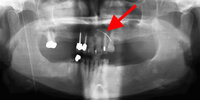

Panoramic radiograph with gutta percha tracking of intra-oral fistula; shows large periapical radiolucency related to failed root canal treatment (note the multiple root canal-treated teeth)

From the personal collection of Melanie S. Lang and Thomas B. Dodson